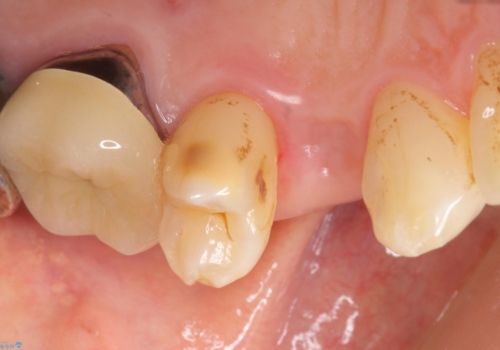

歯がわれた 抜歯してインプラント 50代男性

- 歯ぐきの腫れと痛みを主訴に来院された患者様です。

精査したところ、歯が割れており保存不可能な状態であったためやむなく抜歯しました。

患者様のご希望によりインプラント治療を行いました。